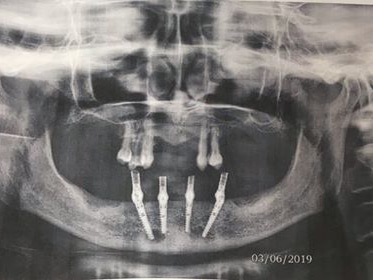

Dr. Carter the owner of Salt Lake Dental was able to provide implants to help his patient chew again. His patients didn’t have their teeth he was able to place implants that provided support to their bridges that Dr. Carter provided so they could chew, smile, and function with their mouth again.